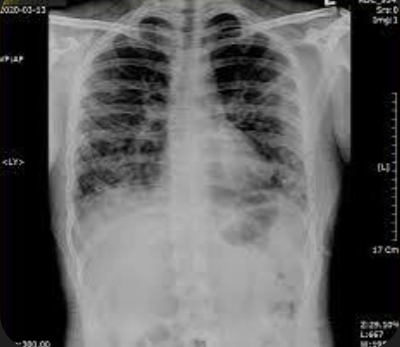

5. 폐렴 증상

폐렴 증상은 질환이 진행되면서 다양하고 심각하게 나타납니다. 주요 증상으로는 고열, 후두통, 가래를 동반한 강한 기침, 흉통, 호흡곤란, 빠른 호흡 등이 있습니다. 가래는 화농성으로 노란색이나 녹색을 띕니다.

폐렴 증상이 심각해지면 입원 치료가 필요하며, 면역력이 약한 경우 합병증이 생길 가능성이 큽니다. 폐렴 치료는 증상에 따라 달라지므로 초기에 의료진의 지시를 따라야 합니다.